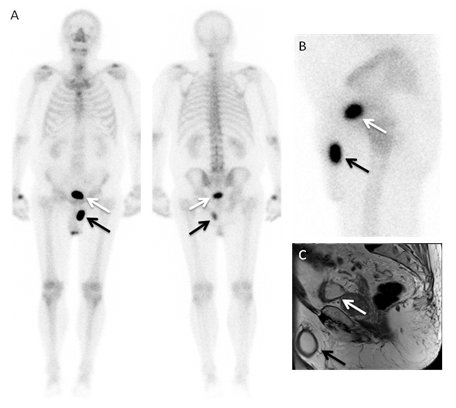

A 72-years-old man with obesity and a recent diagnosis of prostate cancer, was referred to our department for staging, and a 99mTc-HMDP bone scintigraphy was performed. The whole-body images (Figure 1A) revealed no evidence of bone metastasis, but an abnormal accumulation of the radiopharmaceutical was observed in the left anterior extra-pelvic region (black arrows). The lateral pelvic view (Figure 1B) localized the focus on the inguinoscrotal area.  It was identified as an inguinoscrotal hernia of the bladder (IHB) by a pelvic MRI. Selected T2W-MRI sagital and axial slices (Figure 1C&Figure 2) show the urinary bladder (white arrows) and the IHB (black arrow) images in a concordant disposition to the radioactive foci seen in the bone scan (Figure 1B). On physical examination, presented a bilateral inguinal bulge with predominance of the left side, which was more noticeable after weight loss. This bulge worsened with the Valsalva maneuvers and with the bladder filling, and decreased after each urination.

Figure 1 A. Bone scan planar, anterior and posterior, whole body images after intravenous injection of 925 Mbq of 99mTc-HMDP, performed according to the standard protocol, show an accumulation of the radiotracer in the left anterior extra-pelvic region (black arrows), with a similar intensity to that of the bladder (white arrows),

B. Bone scan lateral pelvic view. C. A selected T2W-MRI sagital slice, shows similar findings.

Figure 2 Some T2W-Pelvic MRI transversal slices showing the inclusion of the supero-lateral region of the urinary bladder (white arrows) in the left inguinal hernia.